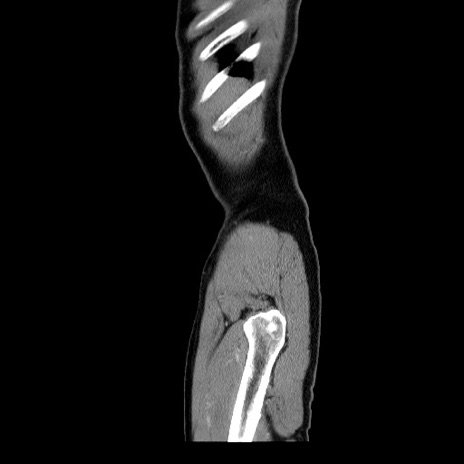

横断像

【症例】60歳代 男性

【主訴】右鼠径部膨隆

【現病歴】1年程前より右鼠径部膨隆あり。自己にて還納可能だったため放置していた。3時間前より右鼠径部の脱出を認め、還納困難となり受診。

【身体所見】右鼠径部に小児頭大の膨隆あり。弾性硬であり、用手還納は困難。左鼠径部にも膨隆を認める。脱出はなし。